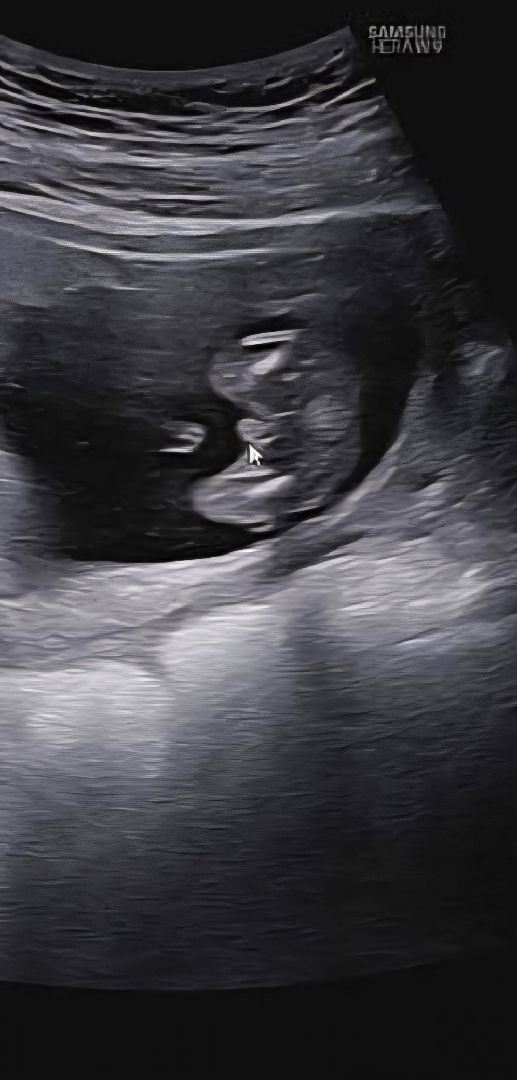

아들 확실하겠죠..?

몇주에요 ~? 16주 미만에는 탯줄이랑 성기랑 구분이 어렵다고 하더라구요

저 16주입니다! 의사선생님은 아들 같다 하시네요.. 🤣